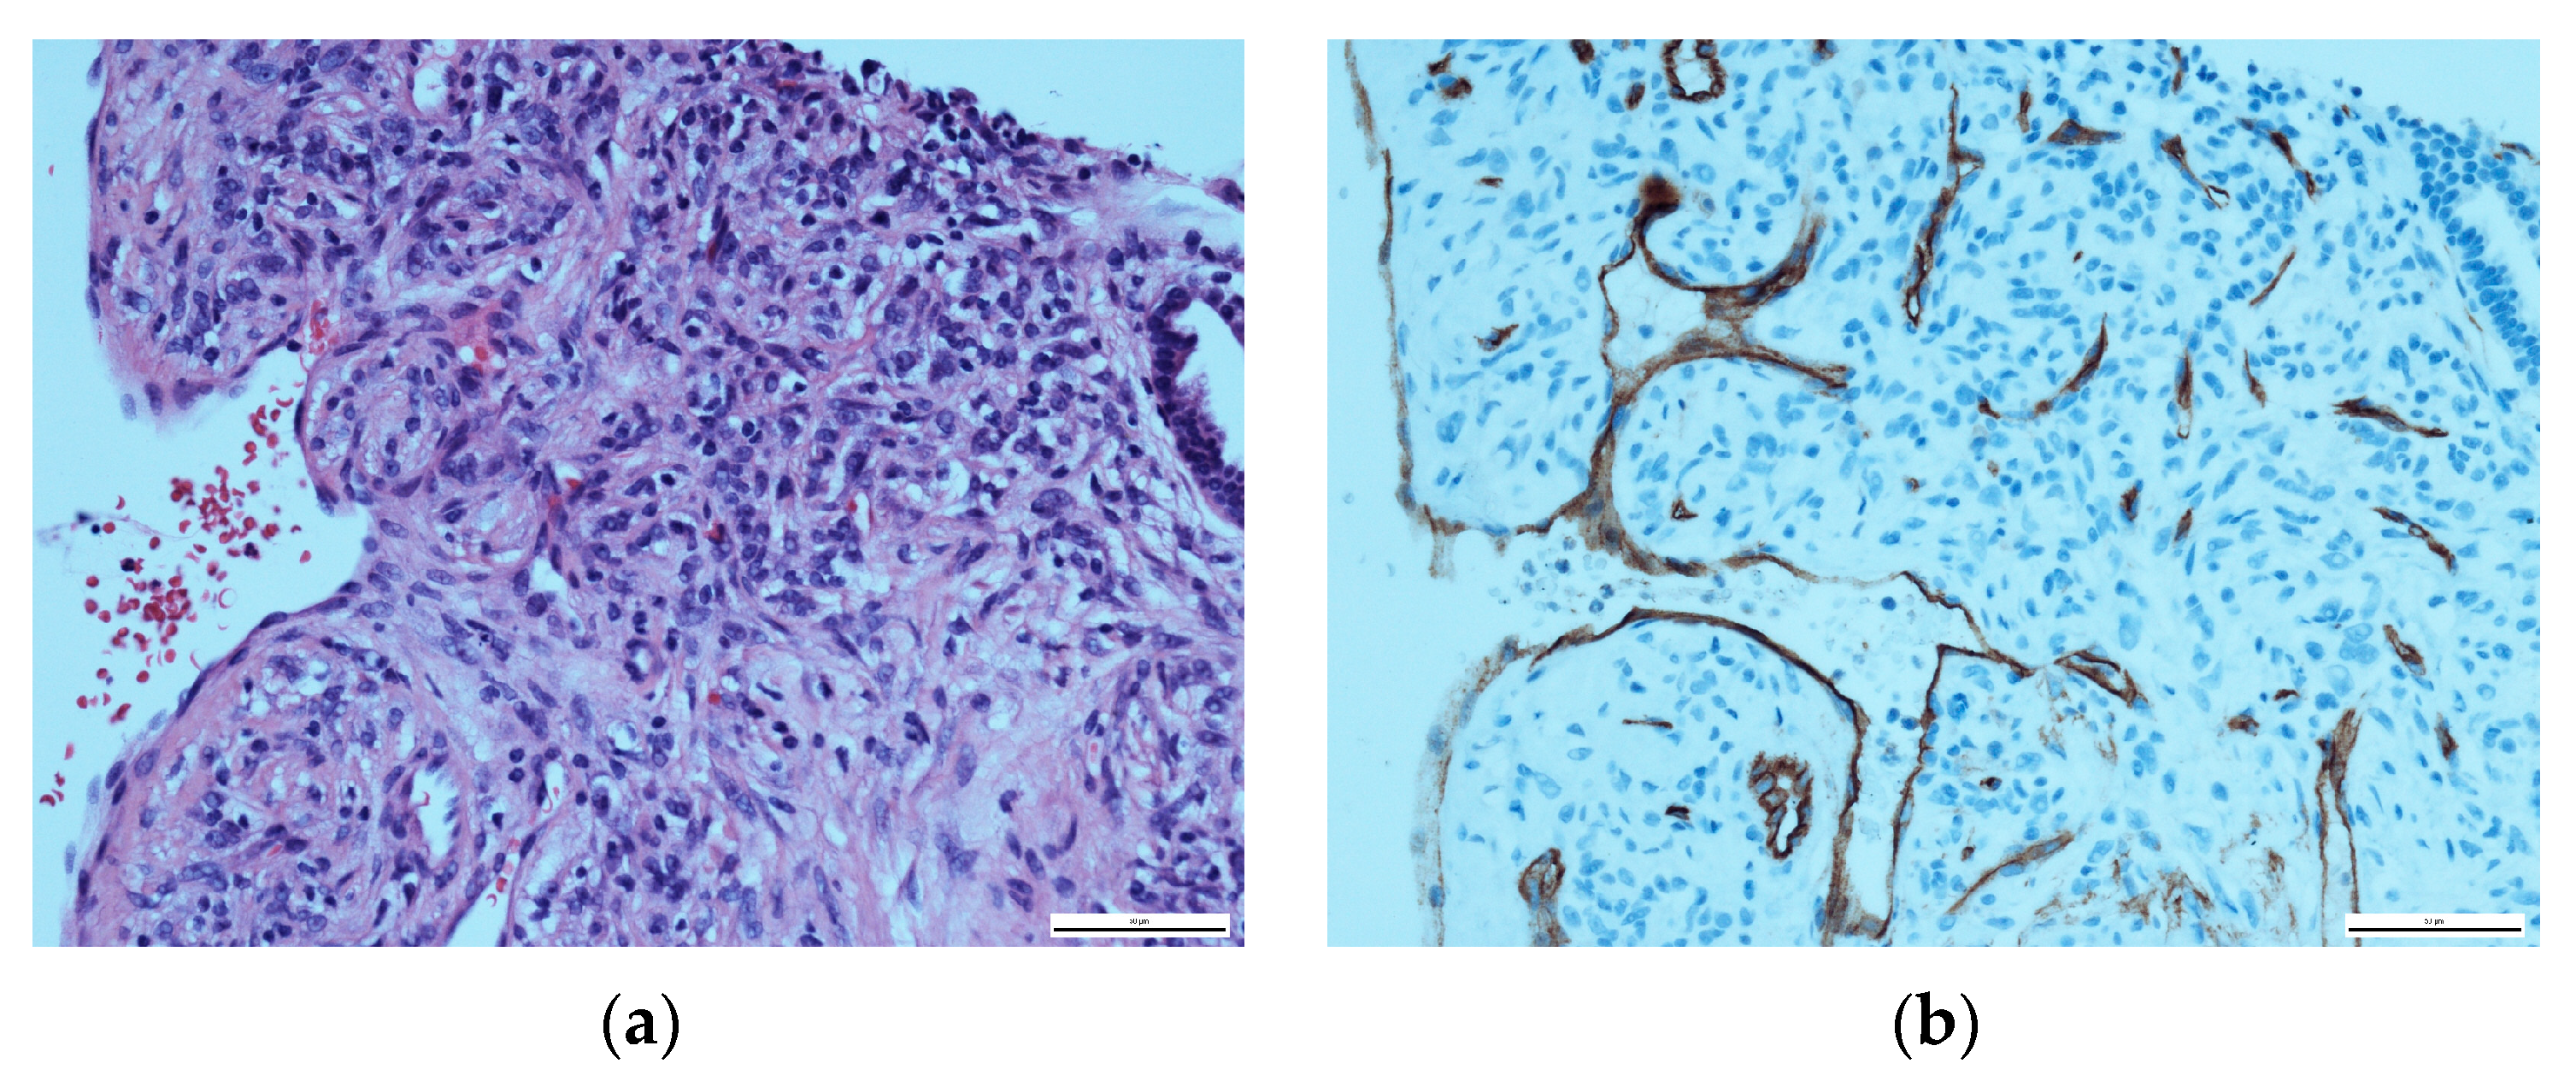

A histopathological evaluation of the punch biopsy showed spindle cells in a swirling formation with hemosiderin-laden macrophages and lipid-laden macrophages, as well as the infiltration of fascia-like collagen bundles (Figure 2a). Limited cell mitosis was observed, whereas tumour necrosis was not. The tumour cells partially tested positive for CD34 as well as CD68 but tested negative for beta-Catenin, Desmin, S100-Protein or STAT6 (Figure 2b). In additional tests, no expression of AE1/3, Caldesmon and Zytokeratin was shown. Proliferation activity (Ki-67-Index) was consistently reported to measure around 10%. At this point in time, a definite diagnosis was unclear. As such, a targeted sequencing assay (FusionPlex Sarcoma v2 Panel) for 63 gene fusions associated with soft-tissue cancers was performed. The tissue exhibited a fusion of LAMTOR1-PRKCD Breakpoint chr11:71814229, chr:53219620. This specific fusion has been correlated with the presence of aneurysmal fibrous histiocytoma, which will be further discussed in the literature review and discussion [16].

Figure 2. Histopathological evaluation of the initial nuchal mass: (a) HE staining, showing swirling spindle cells accompanied by fascia-like collagen bundles at ×400; (b) CD34-positive immunohistochemical staining.